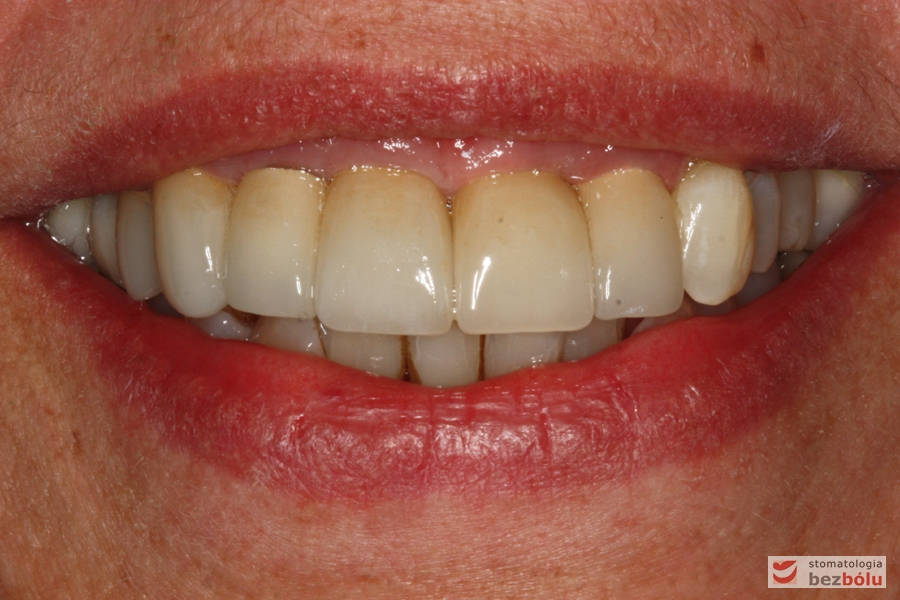

Efekt końcowy leczenia - nowe zęby w uśmiechu

Efekt końcowy leczenia – nowe zęby w uśmiechu